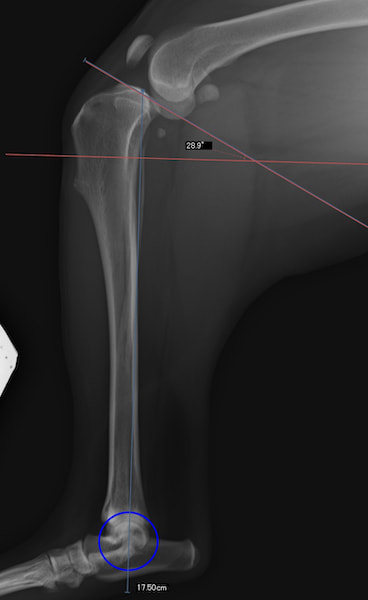

本症例は、走った後に左後肢を挙上していることを主訴に来院されました。触診時に左膝関節のクリック音を聴取、レントゲン検査にて左脛骨の前方変位が認められました。術中に、前十字靱帯の断裂及び内側半月板の損傷、内側の軟部組織の顕著な腫脹を確認。半月板切除、TPLOを実施しました。周囲組織への炎症の波及もあったため回復に時間を要しておりますが、徐々に跛行頻度は減少傾向にあり、現在も経過観察中です。術前に約29°あったTPAは術後に約10°まで矯正されました。

手術前後のTPA(脛骨高平部の角度)を測定しています。

約29°から約10°へ矯正されています。